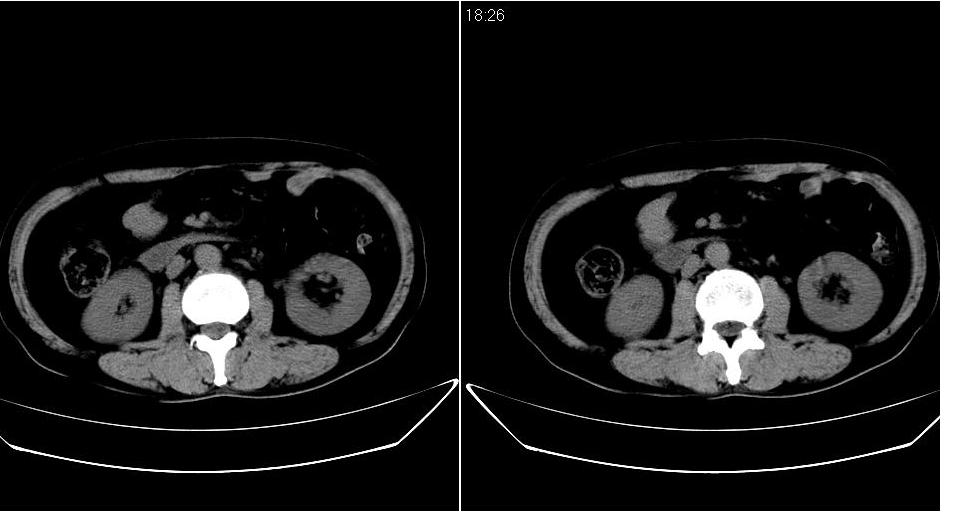

男 48岁,09年8月份在上级医院确诊胰头癌,准备在我院化疗。

胰头体积增大内见低密度影考虑为占位,肿瘤性病变可能性大。

胰头体积增大,外形不规则,密度欠均,支持胰头癌可能性大。